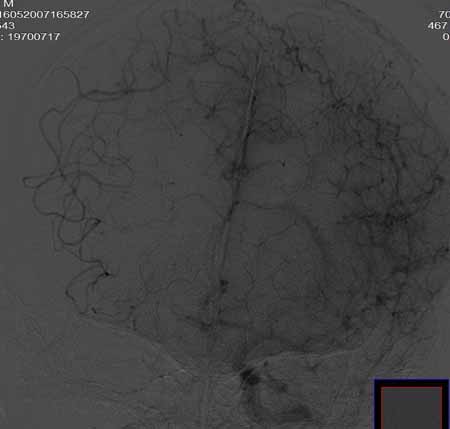

右侧颈总动脉闭塞(血栓形成),左侧大脑前动脉侧支、前交通动脉供应右侧大脑半球

右侧颈总动脉闭塞 ,左侧大脑前动脉侧支、前交通动脉供应右侧大脑半球,后交通部分开放 。缓慢代偿血流,分级3

右侧颈总a闭塞,右颈内颈外未显影,左侧未见异常,并通过wills环代偿右侧大脑半球血供